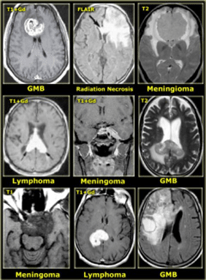

Pemeriksaan penunjang yang penting diperlukan untuk konfirmasi dan melihat lokasi tumor pada otak kita adalah CT scan (Computerized Tomography) dan MRI (Magnetic Resonance Imaging).

Jika ditemukan tumor pada pemeriksaan CT scan / MRI, akan dilanjutkan pemeriksaan PET (Positron Emission Tomography) diperlukan untuk menilai lokasi, batas lokasi tumor, ukuran tumor, dan jaringan sekitar tumor.